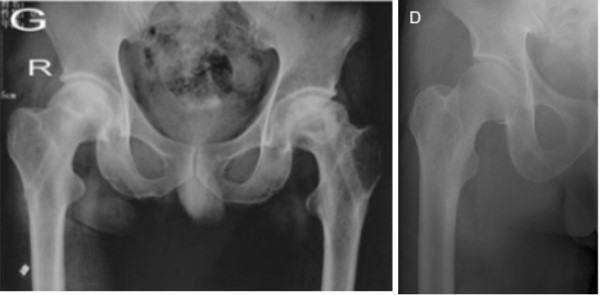

● 股骨头I、II期坏死3.提供足够的力学支撑,防止股骨头塌陷

1.良好的减压效果,有效改善血液循环

2.生物活性材料结合植骨,增强骨融合

3.提供足够的力学支撑,防止股骨头塌陷